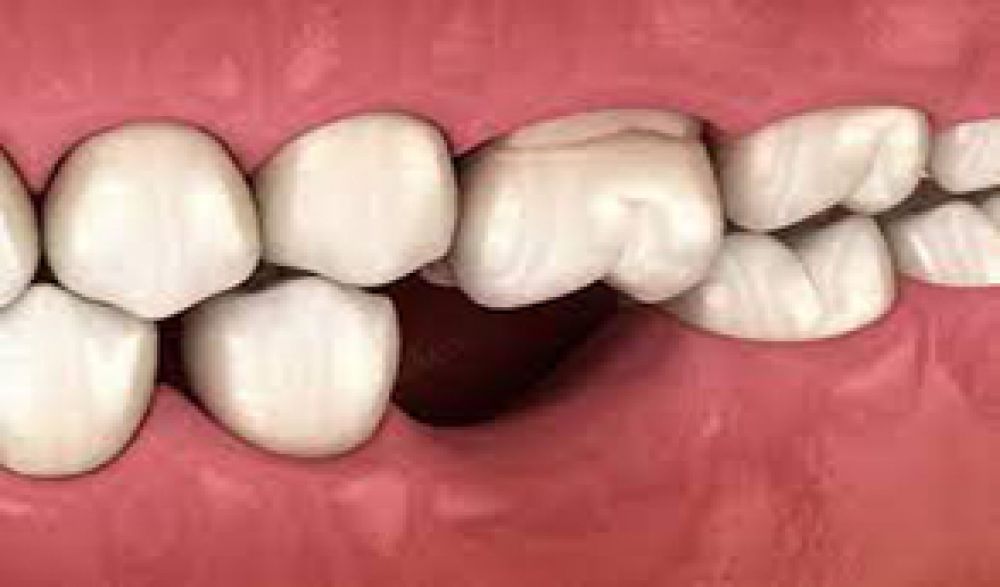

Dentures are removable appliances which are used as a replacement of missing teeth and tissues. They are the artificial teeth which enable normal functioning of human mouth. Dentures are of two types – Complete & Partial. Complete dentures are advised when all the teeth are missing, and partial dentures are applied when some natural teeth are missing. They are custom made especially for a set of teeth and gum line. Complete Dentures fit over the upper teeth and roof and on the lower teeth placed like a horseshoe. They are conventional dentures and are removed during the night for cleaning. Partial Dentures consists of replaced missing teeth attached to artificial gum connected by a metal framework which helps to hold the denture in place. Missing teeth can change the position of other teeth hence partial denture help to overcome this problem and keep the teeth intact.